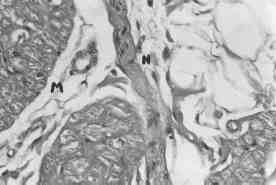

Figura 3: Características microscópicas del nodo AV. Haces pequeños y dispersos de fibras musculares nodales (M) en estrecha relación con una fibra nerviosa (N).